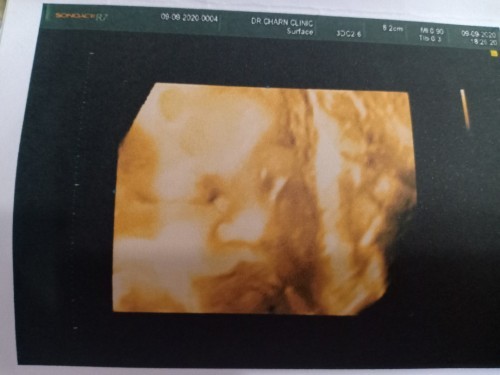

มาอวดรูปตอนซาวด์กันหน่อยค่ะ แม่ๆกำหนดคลอดเดือนไหนบ้างคะ